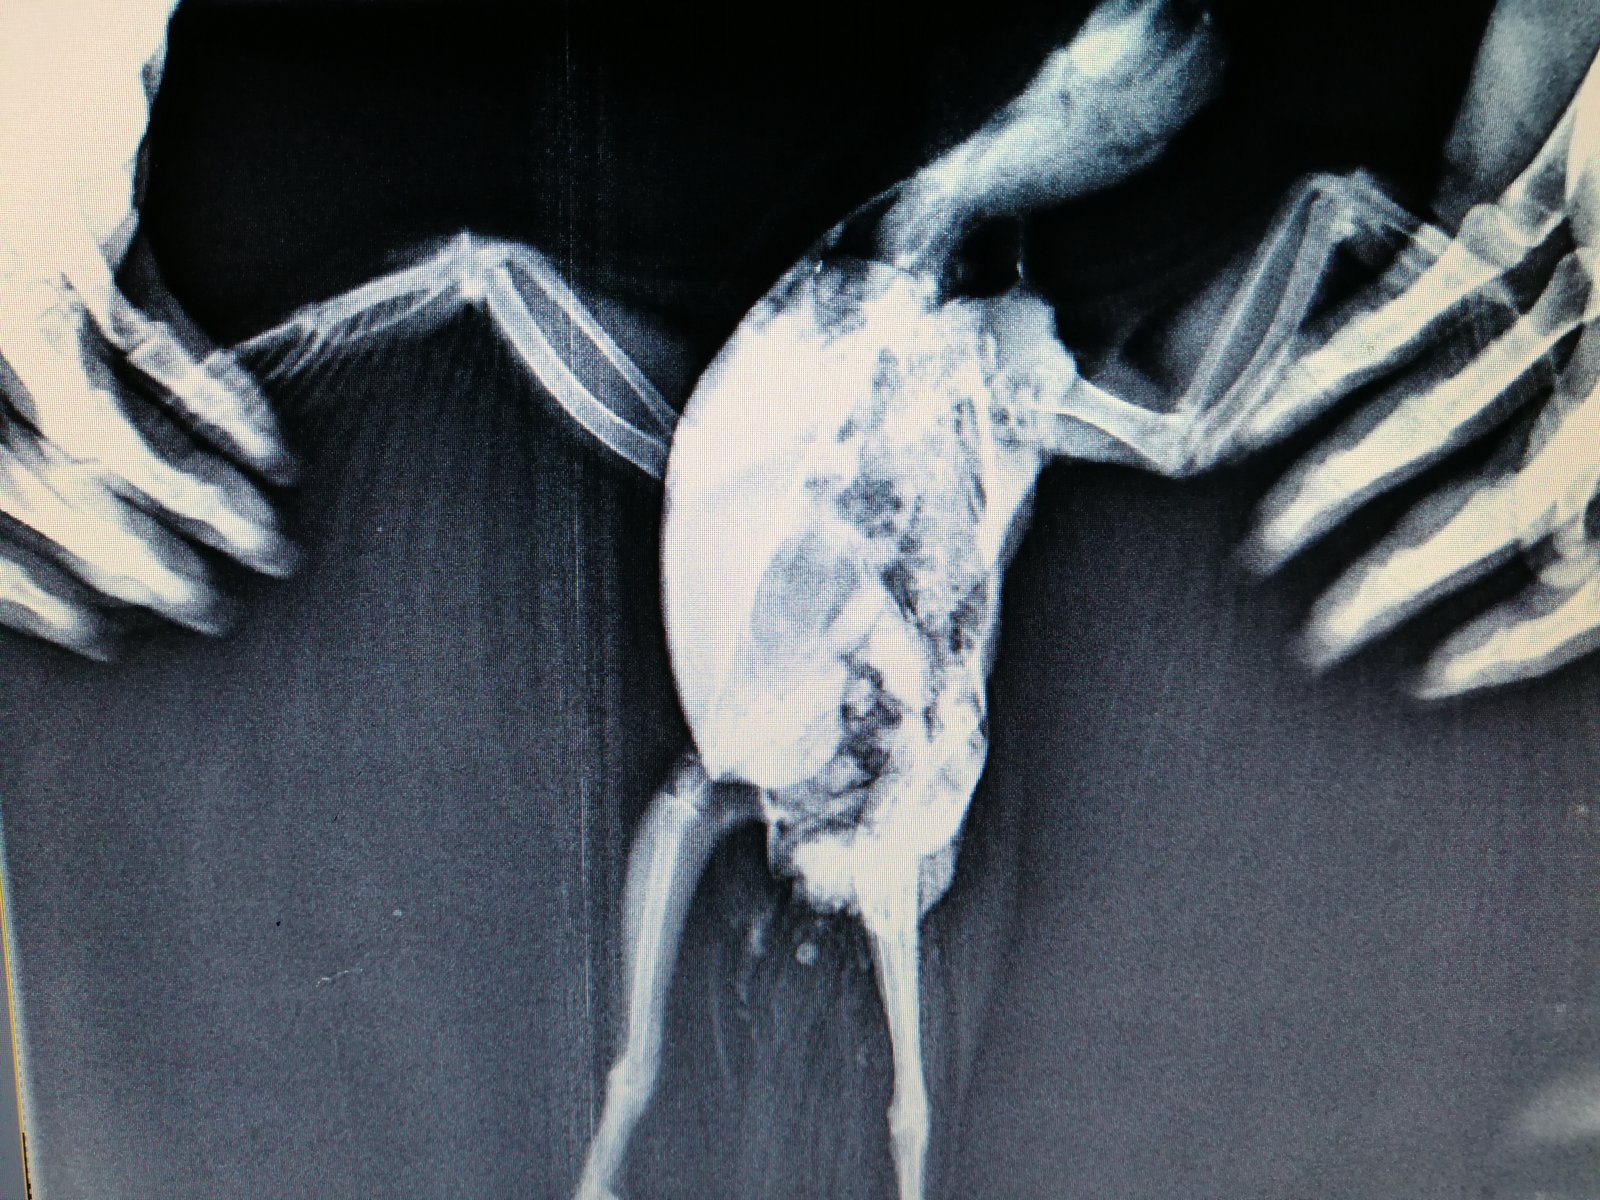

Elena1811 Опубликовано 7 марта, 2020 Автор #113 Опубликовано 7 марта, 2020 Мы старались как могли. Не получается его развернуть полностью из-за левого крыла. Не разворачивается доконца. Боялись сломать

Zosia Опубликовано 7 марта, 2020 #124 Опубликовано 7 марта, 2020 Если есть файлы на флешке- то мне на почту киньте. Т.к. в переснятом виде снимки нечитабельны. zofia68@mail.ru

Elena1811 Опубликовано 11 марта, 2020 Автор #130 Опубликовано 11 марта, 2020 Получила ответ от Зофии. Нужны разъяснения. И некоторые препараты я не могу купить Вот что пишет Зофия: Ну, отличить голубя от голубки я по фото не смогу. Хотя ИМЪО мне видится голубка. И те новообразования в брюшной полости (которые могцт передавливать нервные окончания, идущие к лапкам)- характерны именно для голубок, у меня даже фото есть гранулем, которые у них «рождаются» вместо яиц. Так что ИМХО- итраконазол в дозе 15 мг/кг каждые 12 чсов, нисиатин в дозе 75 000 ед в сутки на 100 гр веса, преднизолон из арсчета 3 мг/кг в сутки. Первый курс- 21 день. Для прикрытия преднизолона- Деринат капли назальные, принимать орально 4 капли в сутки весь курс. Обязательно гепатовте- 0,2-0,3 мл в сутки. По крылу- ваш снимок не дает возможности оценить фатальность нарушений. Но скорее всего- там уже вряд ли что можно сделать (и по-любому это вопрос-не вопрос жизни). ......... У нас беда с преобретением лекарств, рецепты только лишь на аналгин не нужны..